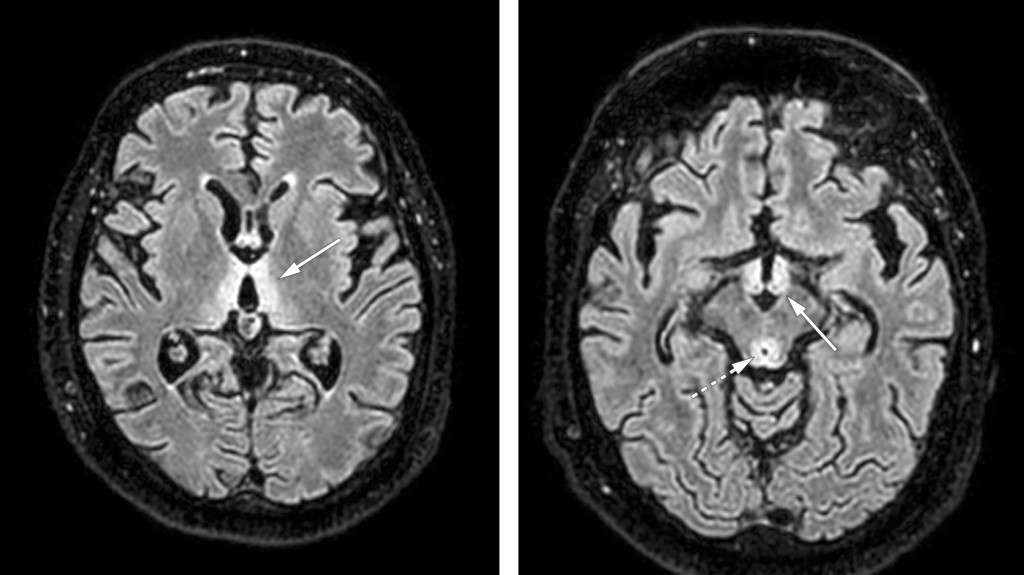

Væskesensitive aksiale MR-bilder (FLAIR) av hjernen viser bilateralt, symmetrisk høyt signal medialt i talamus tilgrensende 3. ventrikkel (pil i bildet til venstre), i corpus mamillare (pil i bildet til høyre) og den periakveduktale grå substans (stiplet pil i bildet til høyre). Nevroradiologiske funn ga mistanke om Wernickes encefalopati.

Nevrologisk undersøkelse avdekket vertikal nystagmus og bilateral partiell abducensparese (se video). Pasienten hadde redusert balanse og styringsvansker i ekstremitetene uten sikker sideforskjell. CT caput avdekket ikke sikker patologi. Funn på supplerende MR caput sammen med symptomtriaden ataksi, oftalmoplegi og mental påvirkning var karakteristiske for Wernickes encefalopati (1, 2). Det ble raskt startet med tiamin 500 mg intravenøst tre ganger daglig i to døgn, deretter 250 mg daglig i 14 dager (3). Komparentopplysninger og en fosfatidyletanol (PEth)-verdi på 0,49 µmol/L bekreftet mistanken om overforbruk av alkohol. Pasienten viste klinisk bedring med behandlingen, men seks måneder etter innleggelsen har han vedvarende utfall forenlig med Korsakoffs syndrom, en følgetilstand til Wernickes encefalopati.